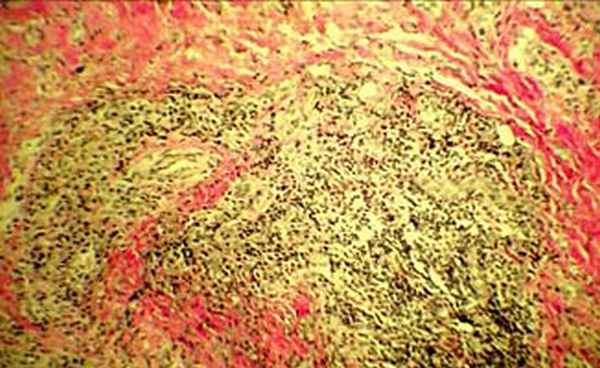

Клиническое течение заболевания позволило заподозрить рецидивирующий полихондрит. Диагноз подтвержден результатами выполненной биопсии левой ушной раковины: перихондральное воспаление, гранулоцитарная инфильтрация (рис. 3а, 3б).

| Рис 3а. Гистологическое исследование биопсии ушной раковины Ув. 1:40 | Рис 3б. Гистологическое исследование биопсии ушной раковины Ув. 1:400 |